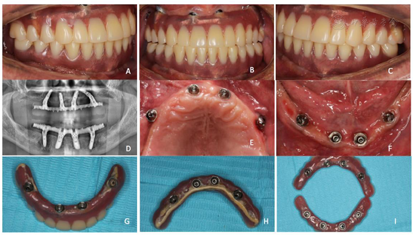

②上颌牙槽嵴黏膜翻瓣,清创炎性软硬组织,平整牙槽嵴顶骨嵴,在自由手操作下分别于12、15、22、25区植入4枚Nobel种植体,旋入复合基台,其中12、15、22区选择植入Nobel Speedy4.0x13mm种植体,25区选择Nobel Active4.3X11.5mm种植体,四颗种植体均利用鼻底皮质骨加强固位,初期稳定性均达到35N.cm(图5)。

③同上颌方法,平整牙槽嵴后于右下颌42、45区分别植入Nobel Speedy4x13mm种植体,均获得35N.cm的初期稳定性,左下颌区牙槽骨骨缺损明显(图6A),延期种植。45区为倾斜植入,放置30度复合基台,42放置球基台(图6B)。下颌种植术后拔除了原预留用作可摘义齿基牙的38、48。下颌过渡义齿利用植入的2枚种植体辅助支持固位,制作种植覆盖义齿过渡修复体(图7)。

术后1个月(2017年3月22日)复诊上下颌术区牙龈黏膜愈合良好,下颌复合基台及球基台周围可见软垢滞留,进行口腔卫生健康教育指导(图8A)。术后3个月(2017年5月17日)复诊X线检查示上下颌种植体骨结合良好(图8B、C)

(3)种植二期修复

①上颌取模一期种植术后5个月后(2017年6月29日)复诊,检查上下颌临时义齿完成,X线示种植体周围骨结合良好,取下过渡义齿,取模拟制作上颌钛支架支持的树脂人工牙种植修复(图9)。拍摄下颌CT检查评估左下颌区牙槽骨愈合良好(图10)。

②左下颌种植一期手术:2017年7月15日局麻下于32、35区植入2枚Nobel speedy4x13mm种植体,旋入复合基台;取下42原放置的球基台更换为复合基台,制取下颌开窗式种植修复印模(图11)。

③种植临床戴牙:利用上颌加工完成的钛支架支持的义齿蜡型,螺丝固定,下颌利用原覆盖义齿修复体局部修理后口内稳固就位作为下颌托,制取咬合记录转移颌位关系。在模型上加工制作树脂修复体,上颌钛支架支持的终义齿修复体恢复至第一磨牙,下颌临时固定修复体暂恢复至第二前磨牙(图12)。戴牙完成后拍摄X线根尖片检查种植体及修复体连接密合(图13)。

(4)种植终义齿修复:下颌种植即刻固定修复后患者原因未能按时复诊,2019年2月(一期手术后24个月,下颌二次种植术后17个月)来诊,X线检查示种植体周围骨结合良好(图14)。制取下颌种植修复印模,制作钛支架支持的树脂修复体,恢复第一磨牙的咬合接触关系,行种植固定终义齿修复(图15)。

医嘱要求戴牙后1、3、6个月、1年、每半年定期复诊维护,口腔卫生指导,检查修复体、修复配件完整性和稳固性,清洁义齿和基台周围,修理修复体出现的裂纹或折裂部分,检查并局部调整咬合。种植修复后3年X线检查示种植体周围骨结合良好,种植体周围未见明显边缘骨吸收(图16,图17)。